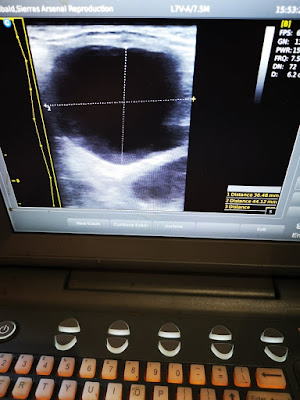

First, I scanned her again to get a baseline of her Uterus and the follicle I was tracking. I was surprised to see how much it had changed in just a matter of hours - the walls were thickening and losing definition in some areas, it had grown considerably, and was developing a pointed end.

Finally, the last step is to ultrasound again to confirm the semen was properly deposited into the uterus, and track the amount of fluid in the uterus over the hours (or days) that follow. The cervix itself only stays open for about 3.5 days after ovulation, so the window of freeing the uterus of fluid is fairly wide, but still needs to be closely monitored. Often the use of Oxytocin does the trick, but sometimes mares need veterinary attention that requires their uterus being filled with sterile fluid and/or medications, then drained and I try avoid that at all costs.